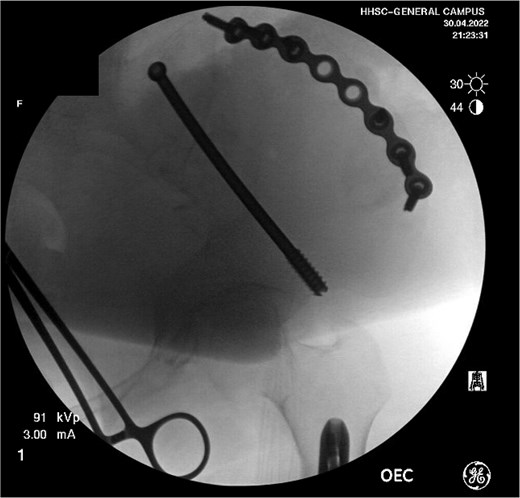

Definitive treatment of her distal femur fracture was performed the following day with a reamed, statically locked retrograde intramedullary nail after consultation with the orthopedic oncology team. The procedure was uncomplicated. For the iliac wing fracture, she was transferred to the local level I trauma center 5 days later for surgery by a pelvic and acetabular specialist. The fracture was addressed via a curvilinear approach to the iliac crest, followed by the application of a contoured pelvic reconstruction plate to the outer table of the iliac crest. Fixation was supplemented with an 8.0 mm partially threaded cannulated screw and advanced antegrade through the supraacetabular corridor (Fig. 4).